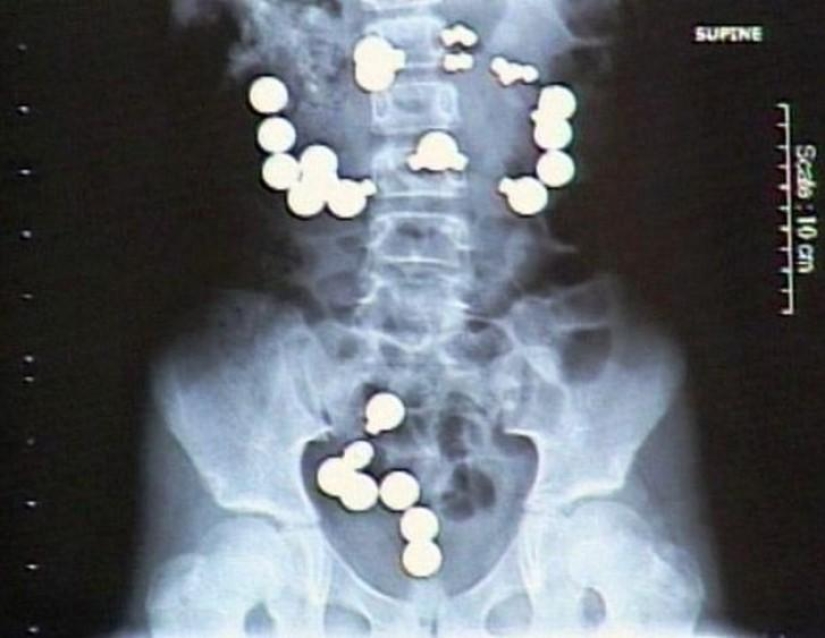

4. Moneda.